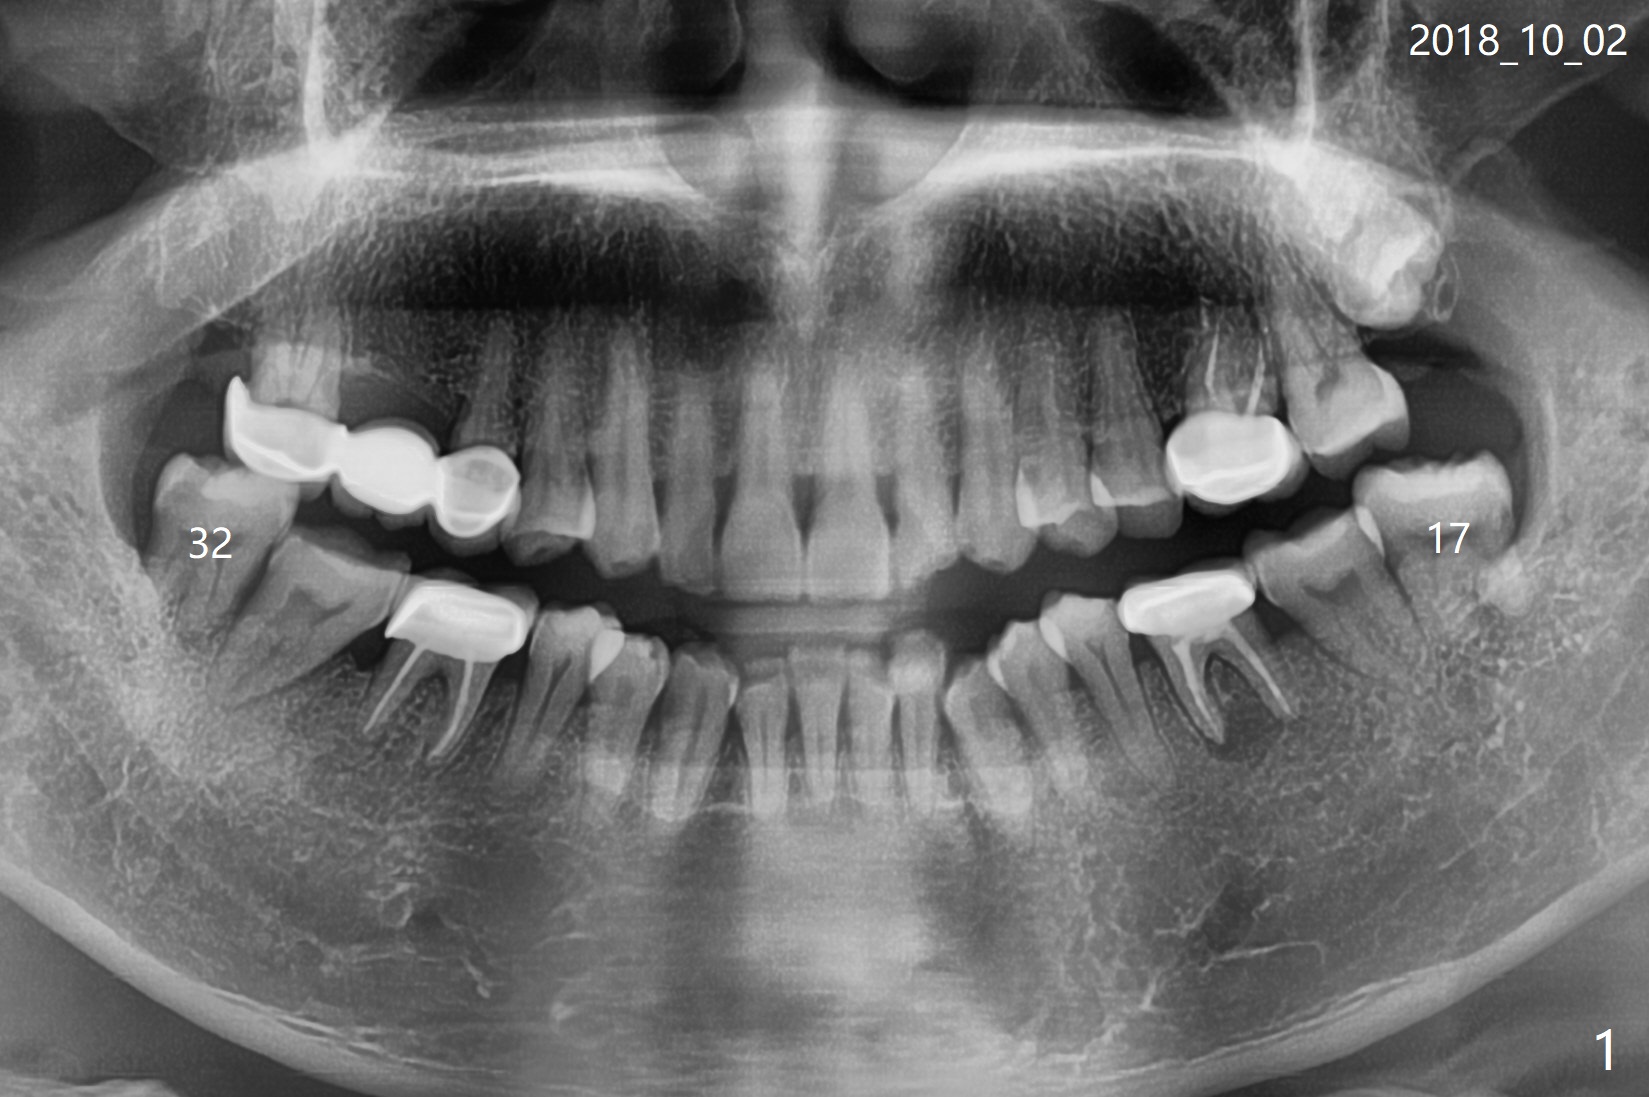

A 43-year-old man without significant medical history requests extraction of #17 and 32 (Fig.1). To prevent distal bone loss at #18 and 31, Osteogen plug is placed in the extraction sockets (Fig.2).